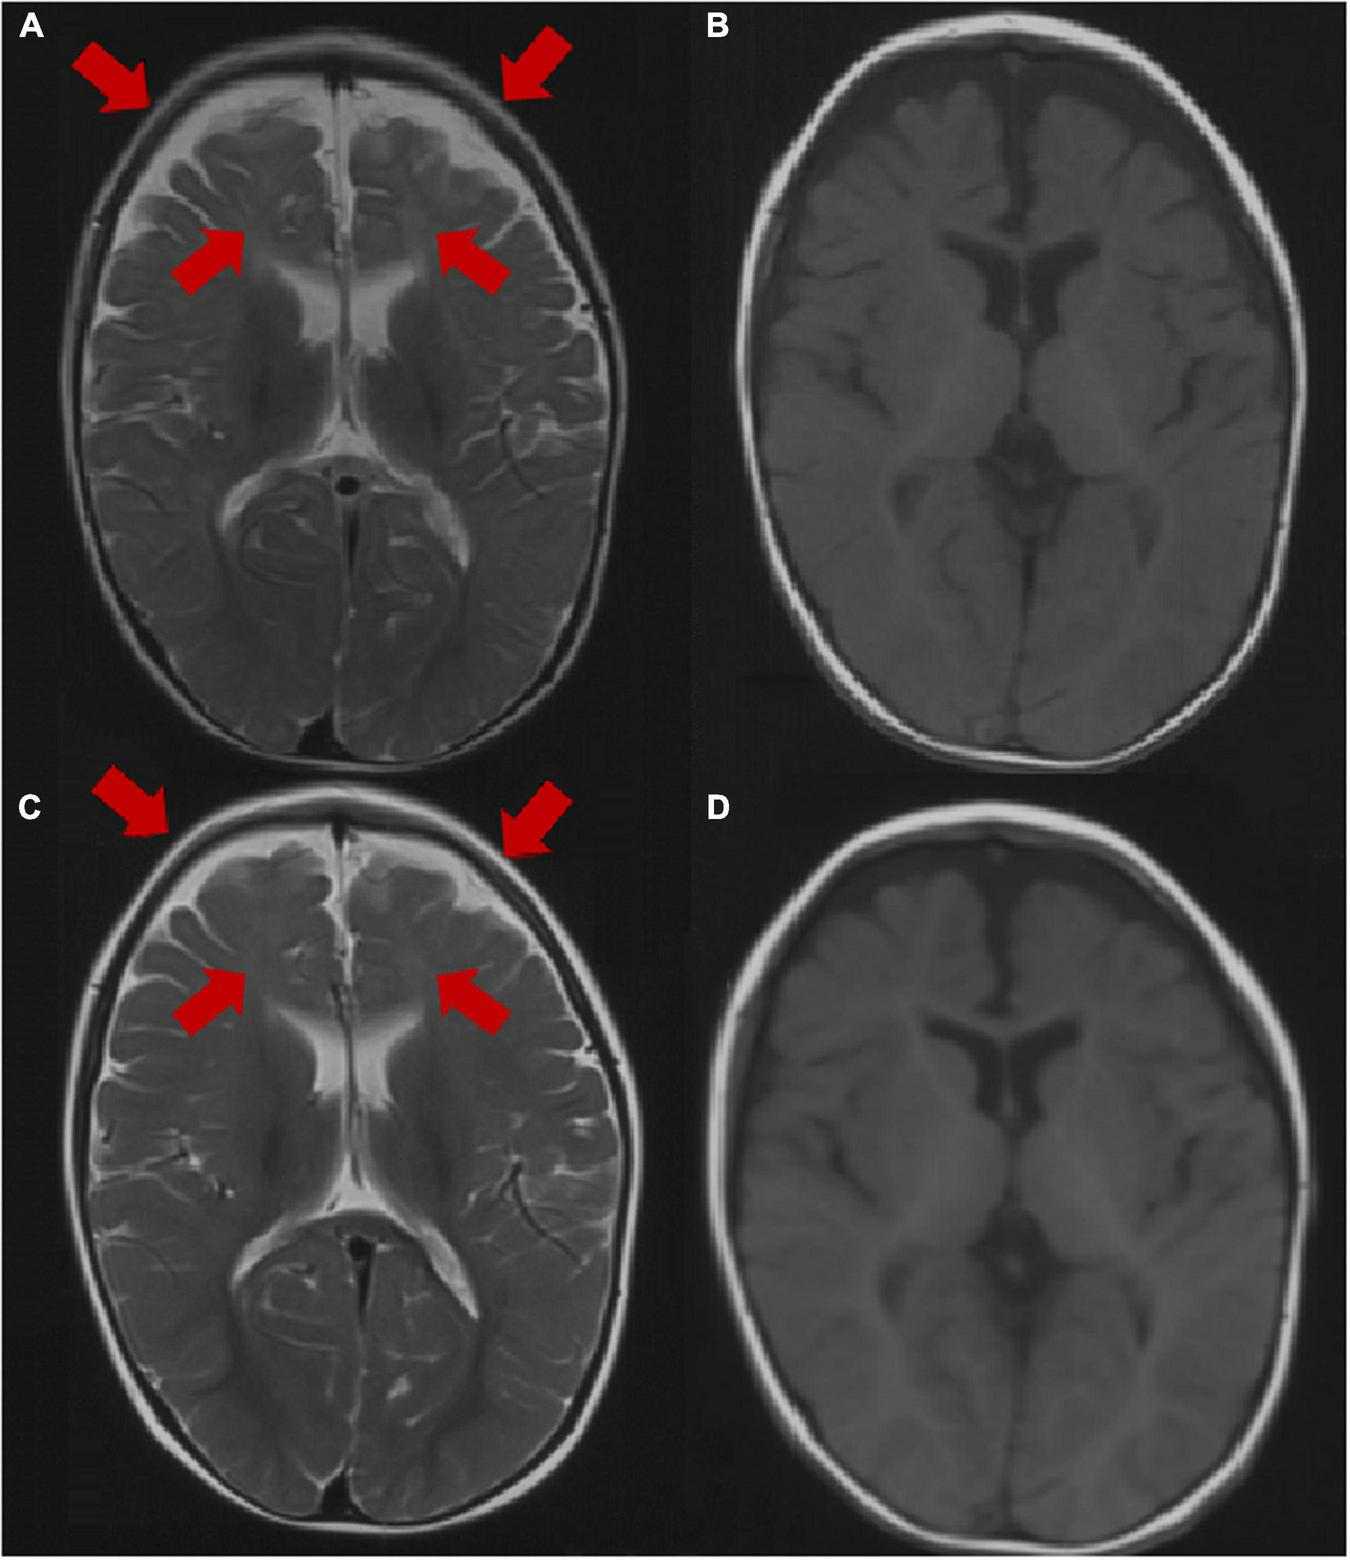

Brain MRI was abnormal in 2 patients (2/31, 6.5%), including dysplasia of the frontotemporal cortex and delayed myelination of white matter in 2 patients (patient 3 and patient 25). The brain MRI of 29 patients was normal at the last follow-up. The brain MRI results of patient 3 are shown in Figure 2.

FIGURE 2

Brain MRI image of patient 3 at the age of 1 year. (A,B) Axial images (T1WI and T2WI) showing dysplasia of the frontal and temporal cortex and delayed myelination. Brain MRI image of patient 3 at the age of 2 years. (C,D) Axial images (T1WI, T2WI) showing dysplasia of the frontal cortex and delayed myelination. The arrow points to the lesion.